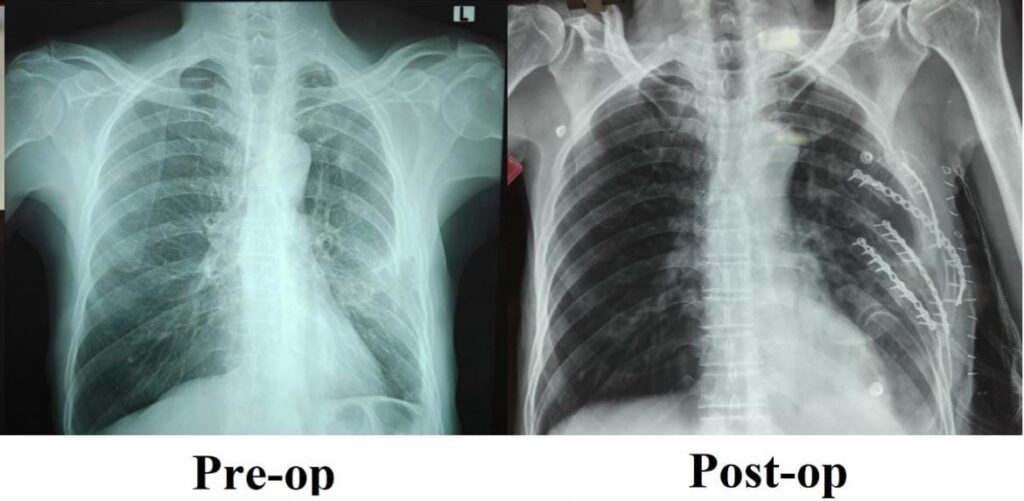

சாலை விபத்து ஒன்றில் சிக்கிய நோயாளி ஒருவருக்கு விலா எலும்புகள் பல இடங்களில் உடைந்திருந்தன. ஒரு மாதத்திற்கும் மேலாக முறையான வலி நிவாரண சிகிச்சைகளும், இயன்முறை சிகிச்சைகளும் அளிக்கப்பட்ட போதிலும், அவர் தொடர்ந்து கடுமையான நெஞ்சு வலியால் அவதிப்பட்டார். எலும்புகள் சரியாக இணையாததாலும், முறிந்த விலா எலும்புகளின் நிலையற்ற தன்மையாலும், ஆழமாக சுவாசிப்பதில் சிரமம், சரியாக தூங்க இயலாமை மற்றும் அன்றாடப் பணிகளைச் செய்ய முடியாத நிலை அவருக்கு நீடித்தது.

நிலைமையின் தீவிரத்தை உணர்ந்த பொது அறுவை சிகிச்சைத் துறையின் இணைப் பேராசிரியர் டாக்டர் விஜயன் P தலைமையிலான குழுவினர், முறிவுகள் ஏற்பட்டிருந்த விலா எலும்புகளை மீண்டும் சீரமைத்து நிலைநிறுத்தும் சிறப்பு அறுவை சிகிச்சையை இவருக்குமேற்கொண்டனர்.

அறுவை சிகிச்சையைத் தொடர்ந்து, இந்நோயாளி வலி குறைந்து, இயல்பாக சுவாசிக்கத் தொடங்கினார். மிக விரைவாகக் குணமடைந்த அவரால் மீண்டும் தன்னம்பிக்கையோடு இயல்பான பணிகளுக்கு இப்போது திரும்புவது சாத்தியமாகியிருக்கிறது.

பொது அறுவை சிகிச்சைத் துறையின் இணைப் பேராசிரியர் டாக்டர் விஜயன் P. இந்த சிகிச்சை செயல்முறை பற்றி பேசுகையில், “விலா எலும்புகள் வலுவின்றி நீண்ட காலம் நிலையற்று இருப்பது, சுவாசத்தையும் மற்றும் உடல் இயக்கத்தையும் ஒட்டுமொத்த நலத்தையும் கடுமையாக பாதிக்கும். விலா எலும்புகளை அறுவை சிகிச்சையின் மூலம் நிலைப்படுத்தியதால், அவருக்கு வலியைக் குறைத்து, நுரையீரலின் செயல்பாட்டை எங்களால் மேம்படுத்த முடிந்தது. பொதுவான சிகிச்சைகள் பலன் தராதபோது, இதுபோன்ற பயனளிக்கும் நவீன அறுவைசிகிச்சைகளின் முக்கியத்துவத்தை இந்த சிகிச்சை முறையின் வெற்றி உணர்த்துகிறது.” என்றார்.